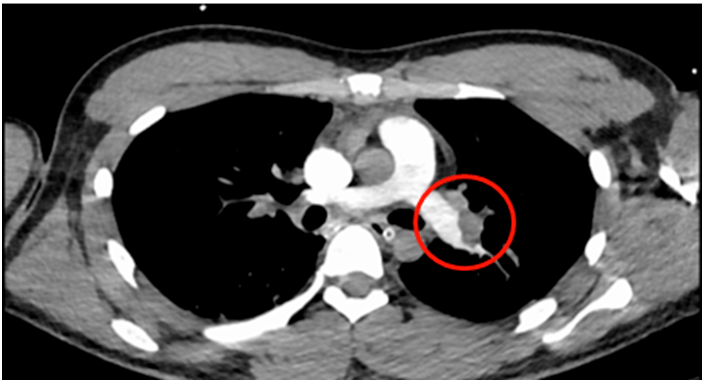

雙下肺動脈主幹完全閉塞

(圓圈所示是堵住肺動脈的血塊)